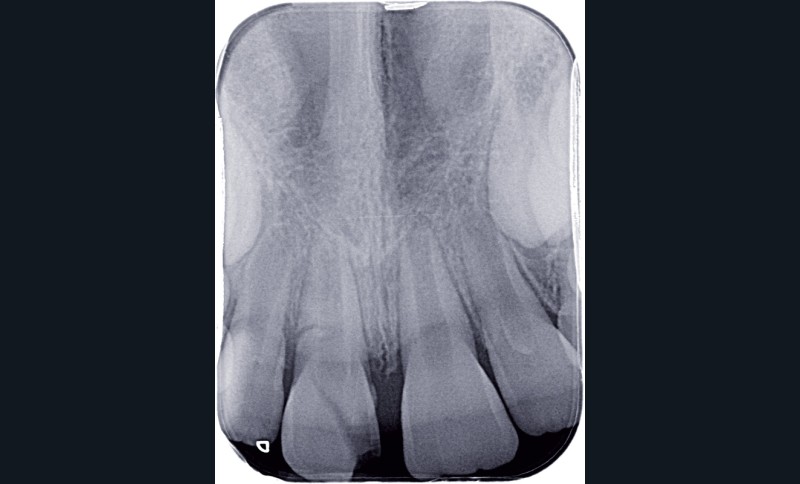

a à d Jeune patiente âgée de 8 ans, adressée suite à un traumatisme survenu 3 semaines auparavant, pour l’extraction de sa 21. La vue clinique montre un saignement ligamentaire, une mobilité coronaire et une fracture coronaire amélodentinaire longitudinale partant de l’angle mésial et se poursuivant en direction radiculaire sous-gingivale (a). Un test de vitalité positif indique que la dent est vitale, la radiographie permet de poser le diagnostic de fracture coronoradiculaire, et d’objectiver l’immaturité radiculaire (stade 8 de Nolla) (b). Une contention est mise en place et la plaie dentinaire coronaire est scellée au mieux par collage afin de limiter le risque d’une complication infectieuse (c). A 15 jours la dent est vivante et aucune complication n’est apparue (d). La patiente est revue après 3 mois pour déposer la contention, le test de vitalité est positif, et la radiographie de contrôle montre une apexogenèse en cours (e). Cependant la gencive s’est invaginée dans le trait de fracture (f). La zone est débridée sous microscope (g) puis scellée et reconstituée à l’aide d’un adhésif SAM et d’un composite fluide (h). Le contrôle radiographique à 6 mois est satisfaisant (i). Ce cas clinique illustre le fort potentiel des pulpes jeunes et du ligament alvéolodentaire à résister aux agressions et à assurer les fonctions dentinogénétiques et l’édification radiculaire.